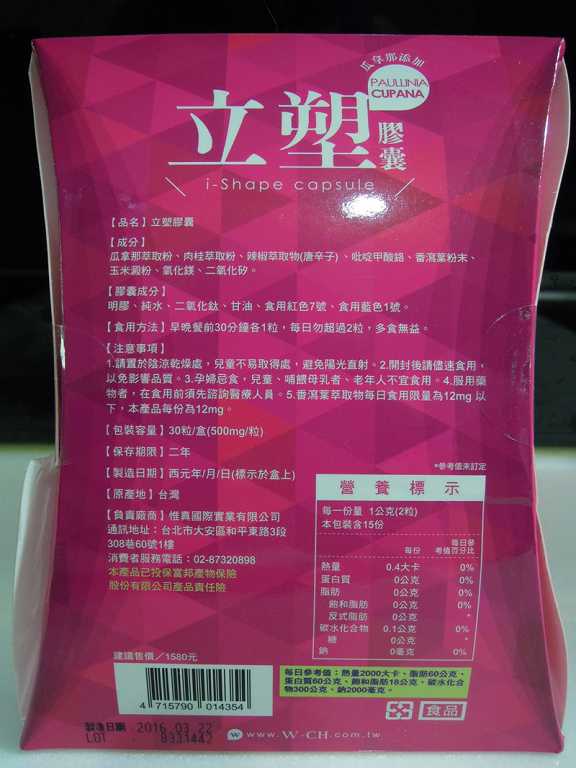

每一盒Supercut塑魔纖立塑膠囊都有三小包,每一小包有10顆膠囊

Supercut塑魔纖立塑膠囊的成分有:瓜拿那萃取粉、肉桂萃取粉、辣椒萃取物(唐辛子)、吡啶甲酸鉻、番瀉葉粉末、玉米澱粉、氧化鎂、二氧化矽。

食用方式:早晚餐前30分鐘各1粒,每日不超過2粒。(多食無益)

包裝是桃紅色的

番瀉葉萃取物每日食用限量為12mg以下,